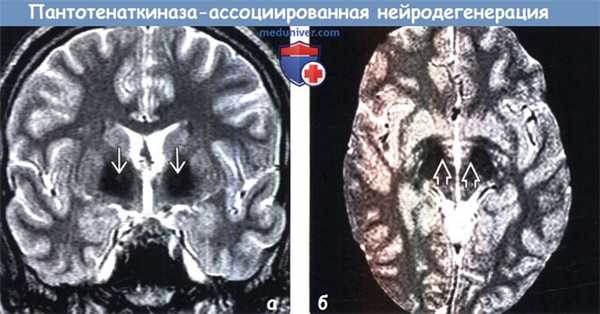

• Лучший диагностический критерий: симптом «глаза тигра» = диффузное снижение интенсивности сигнала на Т2-ВИ от бледных шаров с гиперинтенсивными очагами в их медиальных отделах:

о Очень характерен для ПКАН

(а) МРТ, Т2-ВИ, аксиальный срез: у пятилетнего ребенка с диагнозом детский церебральный паралич определяется характерный для пантотенаткиназа-ассоциированной нейродегенерации (ПКАН) симптом «глаза тигра»: симметричные гиперинтенсивные очаги в медиальных отделах гипоинтенсивных бледных шаров.

(б) МРТ-исследование того же пациента четыре года спустя по поводу дистонии, Т2-ВИ, аксиальный срез: отмечается уменьшение интенсивности сигнала от «глаз» и их размеров на фоне снижения интенсивности сигнала от окружающих отделов бледных шаров. На момент исследования очевидная потеря объема мозговой ткани, особенно в лобных долях. (а) МРТ, Т2-ВИ, корональный срез: у этого же пациента в возрасте 9 лет определяется аномальное снижение интенсивности сигнала от бледных шаров и черной субстанции.

(а) МРТ, Т2-ВИ, корональный срез: у пациента с классической формой пантотенаткиназа-ассоциированной нейродегенерации (ПКАН) определяется классический симптом «глаза тигра» с мелкими гиперинтенсивными очагами, расположенными в медиальных отделах бледных шаров и окруженными аномальным гипоинтенсивным сигналом от последних.

(б) МРТ, Т2* GRE, аксиальный срез: у пациента с классической формой пантотенаткиназа-ассоциированной нейродегенерации (ПКАН) определяется эффект «выцветания» в виде гипоинтен-сивного сигнала от нижних отделов бледных шаров и черной субстанции. При диагностической визуализации аномальное отложение железа в черной субстанции становится более заметным по мере прогрессирования заболевания.